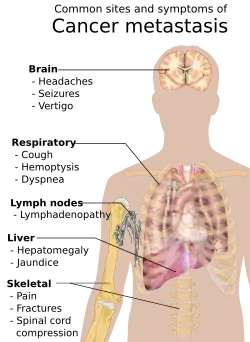

Metástase

O câncer pode se espalhar a partir do seu local original de propagação através da disseminação linfática para os linfonodos regionais, ou pelo sangue para locais distantes, processo conhecido como metástase. Quando o câncer se espalha por uma rota sanguínea, normalmente se espalha por todo o corpo. No entanto, "sementes" de câncer crescem em determinados locais. Os sintomas de cânceres metastáticos dependem da localização do tumor e podem incluir linfadenopatia, hepatomegalia ou esplenomegalia, dor ou fratura dos ossos afetados, além de sintomas neurológicos.[43]

Metástase

A metástase é a propagação do câncer para outros locais do corpo. Os novos tumores são chamados de tumores metastáticos, enquanto a massa original é chamada de tumor primário. Quase todos os tipos de câncer podem ter metástase.[104] A maioria das mortes por câncer ocorrem devido a propagação do câncer, a partir do seu local inicial, para outros órgãos.[105]

A metástase é muito comum nos últimos estágios do câncer e pode ocorrer através do sistema circulatório, do sistema linfático, ou de ambos. Os passos típicos da metástase são a invasão local, o intravasamento para o sangue ou a linfa, a circulação através do corpo, o extravasamento para o novo tecido, a proliferação e a angiogênese. Diferentes tipos de cânceres tendem a ter metástase para órgãos específicos, mas no geral os lugares mais comuns para metástases ocorrerem são pulmões, fígado, cérebro e ossos.[104]